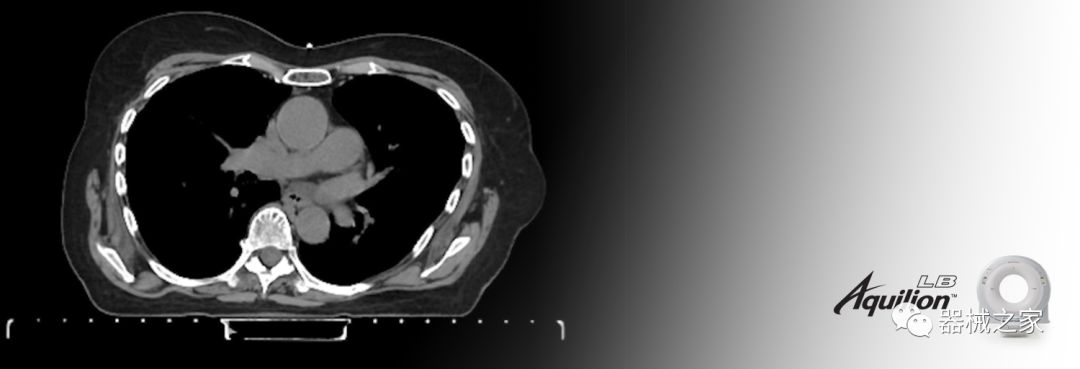

Aquilion LB專為滿足腫瘤學(xué)挑戰(zhàn)而設(shè)計(jì),同時(shí)優(yōu)先考慮患者護(hù)理。Aquilion LB的內(nèi)徑為90 cm,能夠幫助復(fù)雜的患者設(shè)置并提高患者的舒適度。CT模擬定位可以輕松鏡像放射治療定位,更加自信。該系統(tǒng)采用0.5 mm x 16排(32層)PUREViSION探測(cè)器技術(shù),70 cm視野,AIDR 3D和SEMAR技術(shù)。